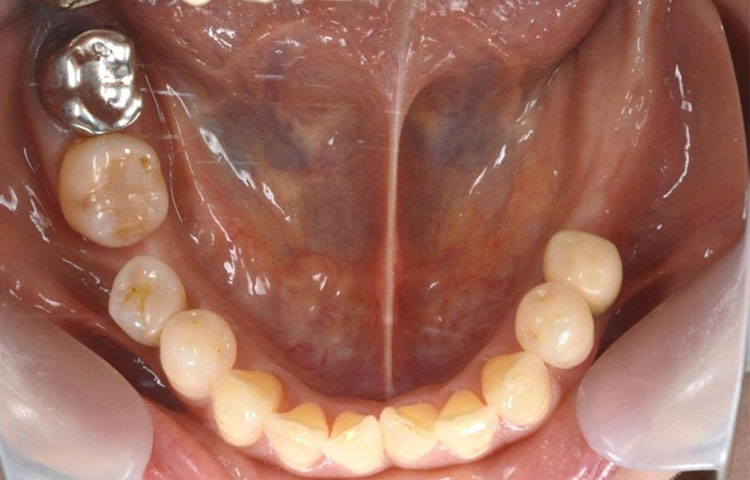

All-on-4症例 Case1

Treatment cases

Before

After

インプラント治療は、咀嚼機能の改善だけでなく、 口腔周囲筋の発達により見た目の若返りにも貢献してくれます。